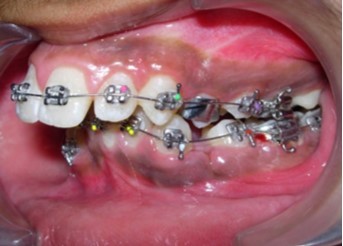

Initial alignment was done with upper and lower 0.014-inch nickel titanium archwires (Figure 6a,Figure 6b,Figure 6c). This was followed with 0.016-inch nickel titanium archwires. Space for blocked out 42 was created by an open coil spring on a 0.018-inch stainless steel archwire. Deep bite was corrected with a lower 0.016-inch reverse curve nickel titanium wire. Extraction spaces in the maxillary and mandibular dental arches were closed with 9mm nickel titanium retraction coil springs attached to crimpable hooks on 0.017 x 0.025-inch stainless steel archwires and finishing and detailing was completed with 0.019 x 0.025-inch stainless steel archwires.

Figure 6a.Initial levelling and alignment – Upper / Lower 0.014-inch nickel titanium wires – Frontal

Figure 6b.Initial levelling and alignment – Upper / Lower 0.014-inch nickel titanium wires – Right

Figure 6c.Initial levelling and alignment – Upper / Lower 0.014-inch nickel titanium wires – Left